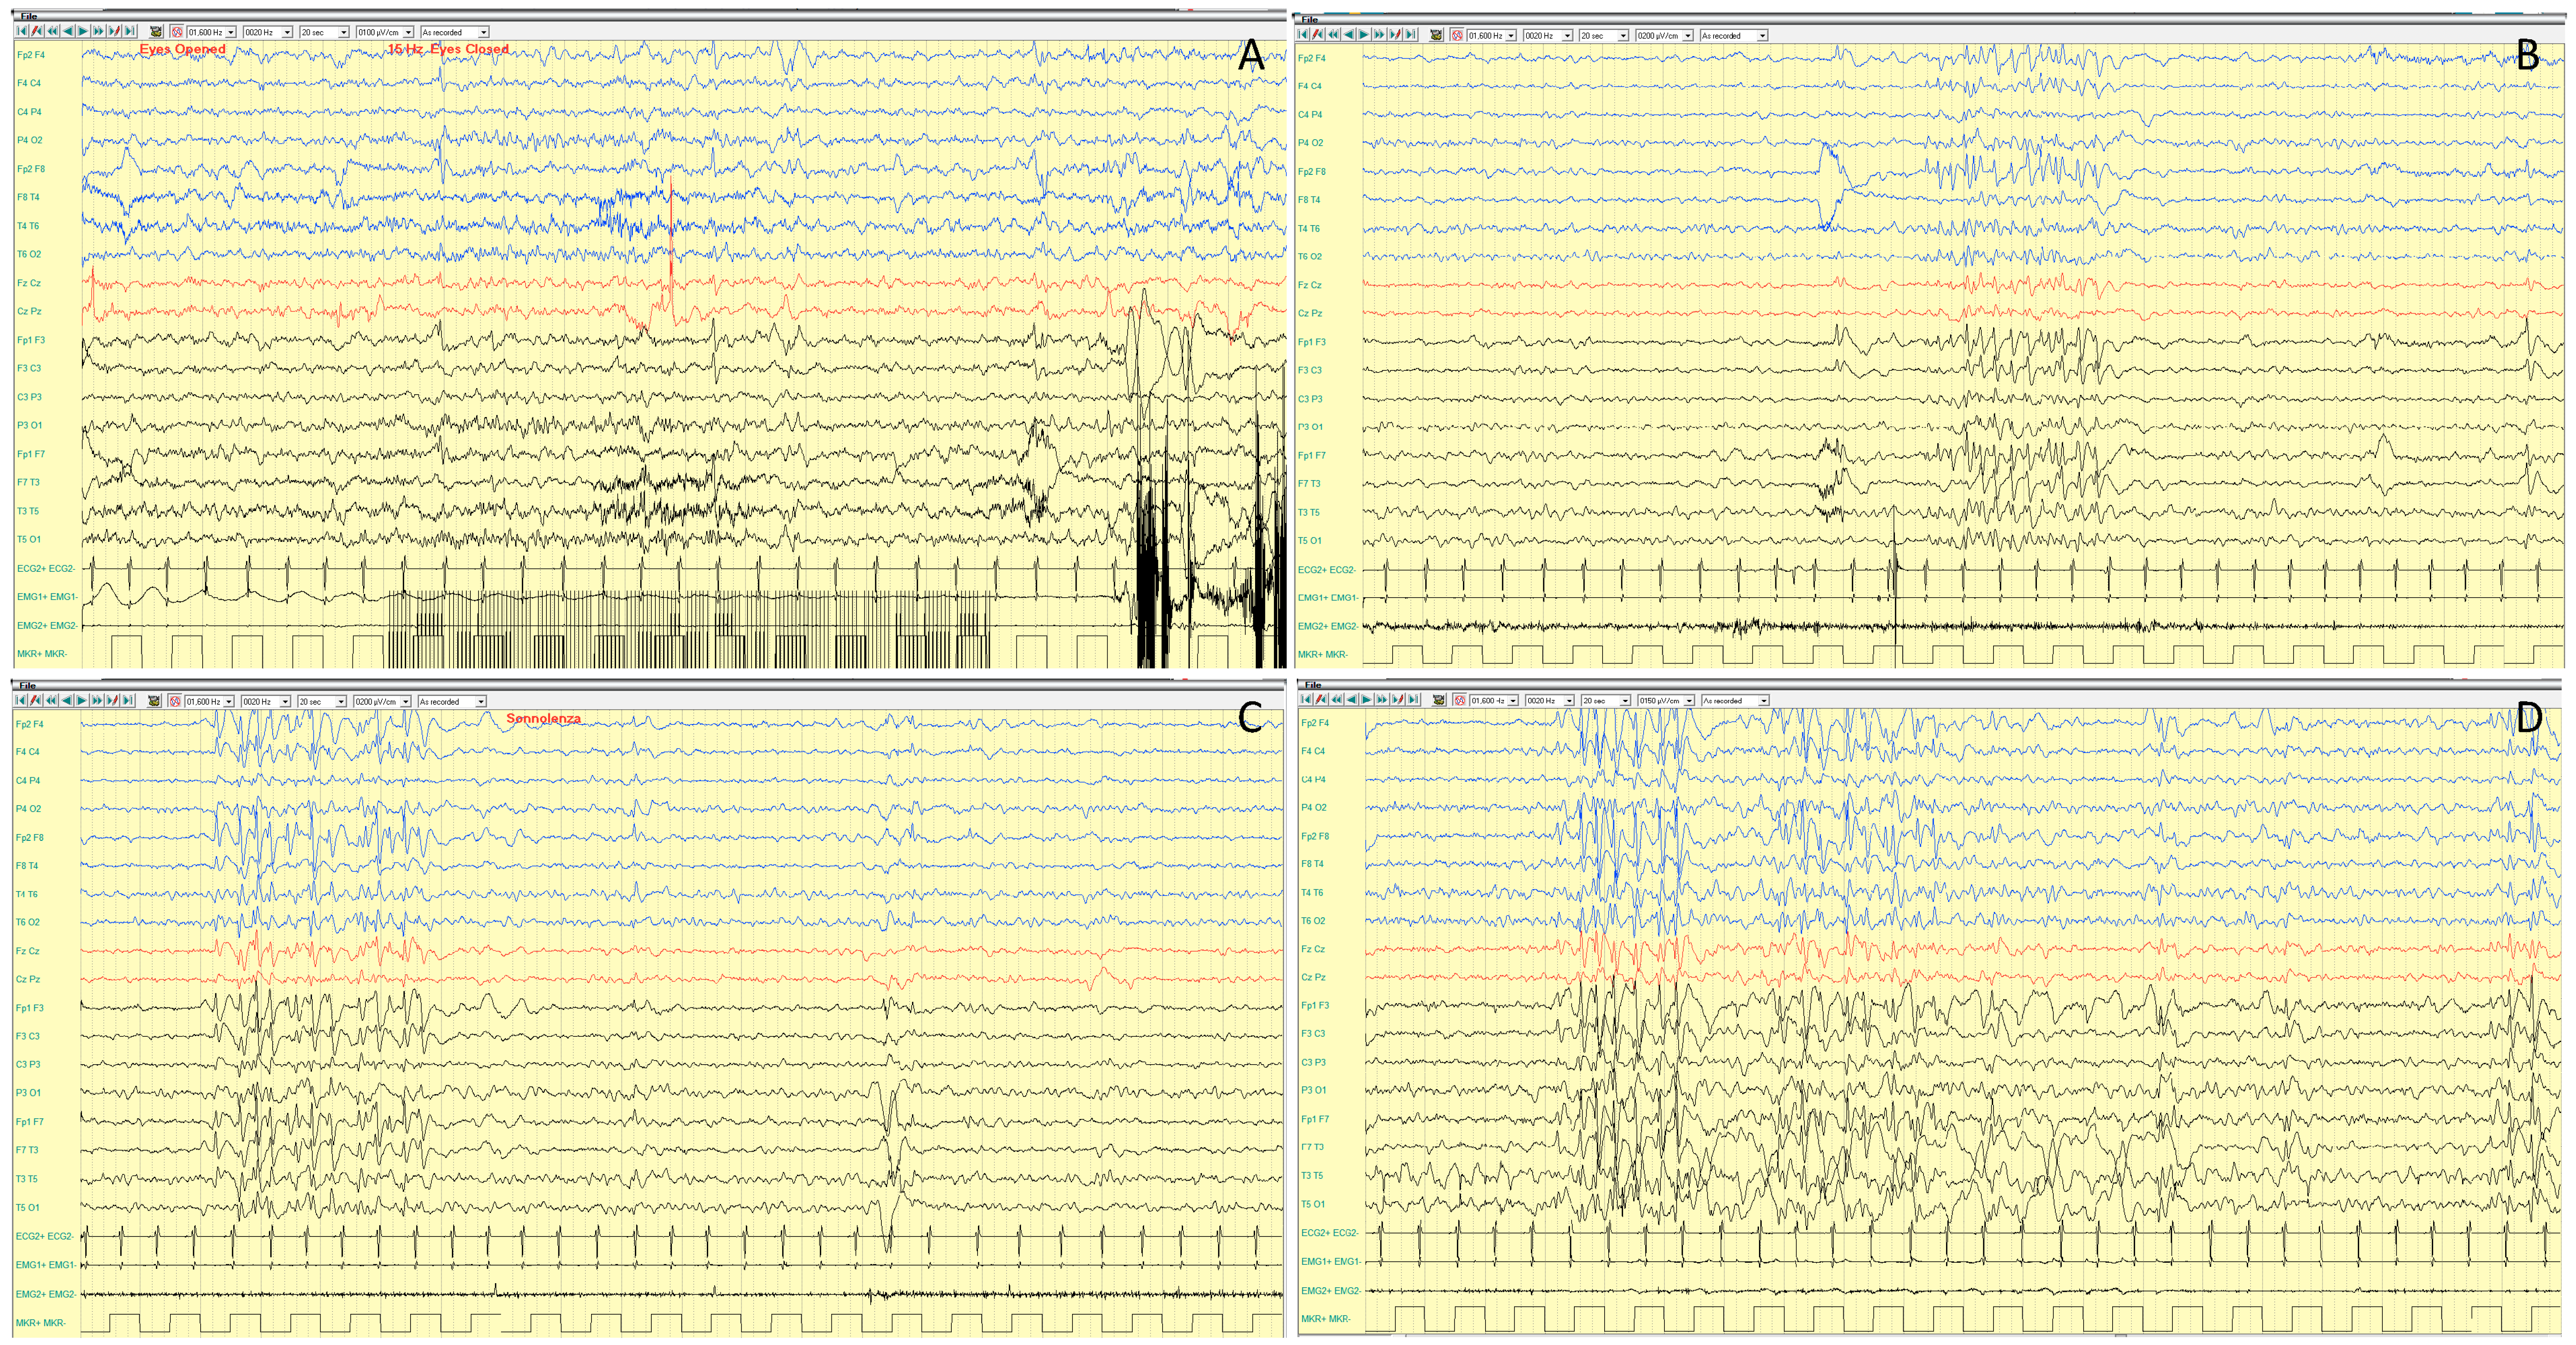

4.1.3. EEG Features